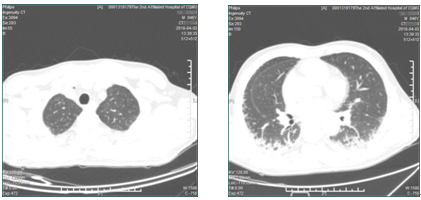

2018年3月22日,患者突然出现右侧颈根部皮下气肿,胸部CT平扫示颈根部及纵膈积气(见下图),双肺间质性肺炎,考虑病情加重,立即下达病危通知,持续氧疗,调整免疫抑制剂,同时护理团队加强护理治疗。

通过全科室医护人员的共同努力,患者的皮下气肿、纵膈气肿逐渐吸收,2018年4月3日复查胸部CT(见下图),患者的皮下积气、纵隔积气较前明显吸收减少,双肺间质性肺炎无明显变化,目前病情稳定,拟近日出院。